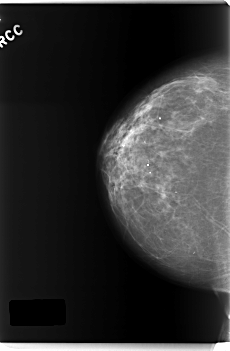

C_0218_1.RIGHT_CC

RIGHT_CC LINES 5952 PIXELS_PER_LINE 3896 BITS_PER_PIXEL 12 RESOLUTION 50 NON_OVERLAY